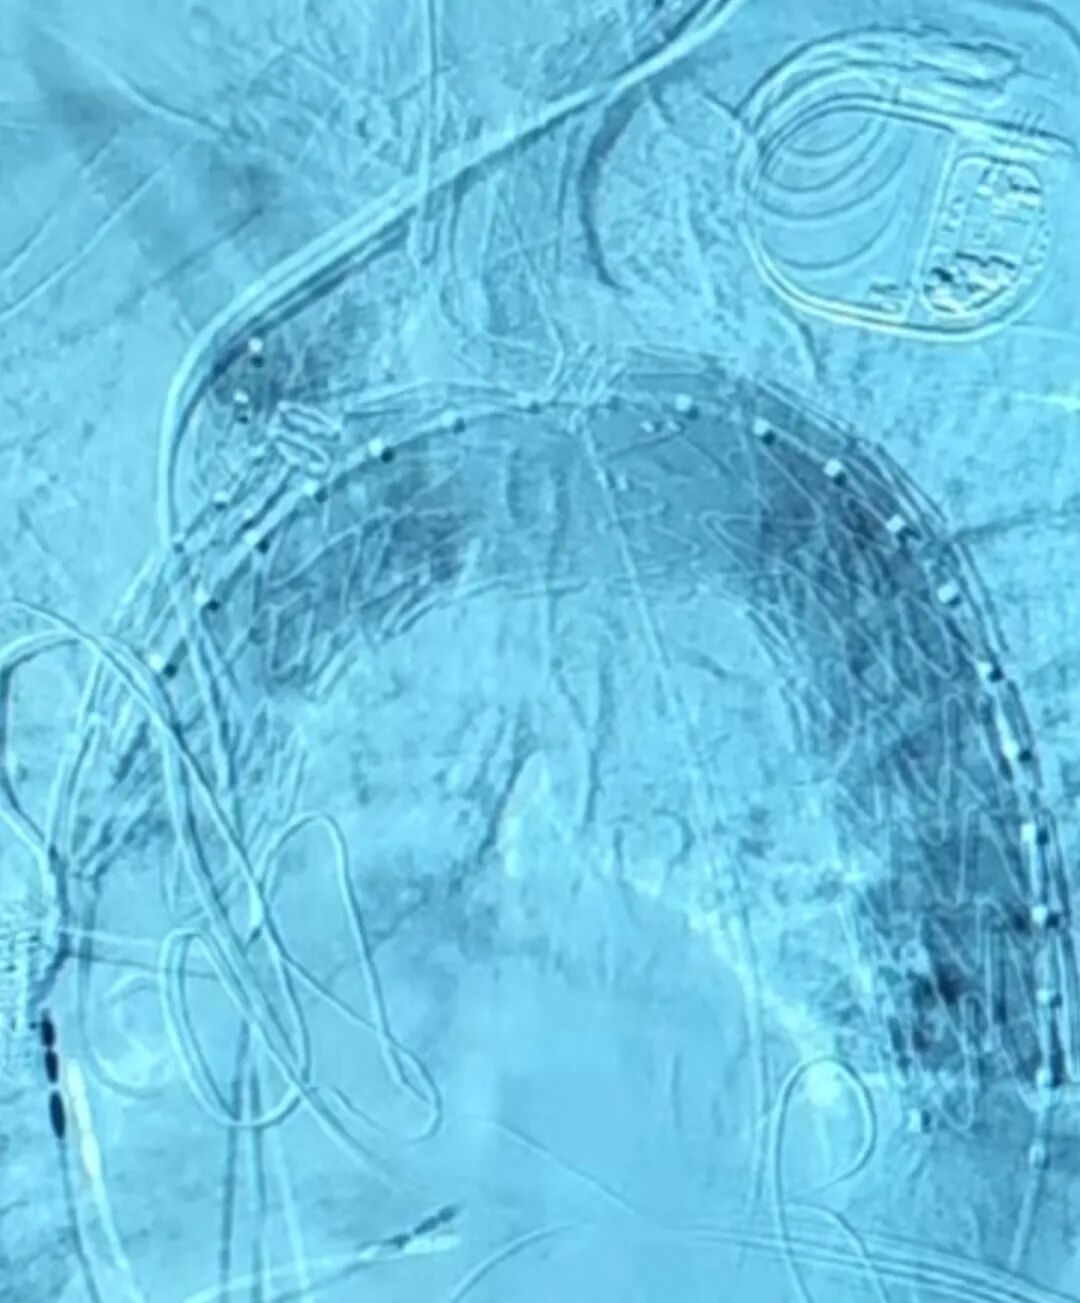

新加坡病例分享

新加坡病例手术在陈笃生医院(Tan Tock Seng Hospital)由Glenn Tan教授及其团队实施。该患者诊断为主动脉弓动脉瘤,瘤体累及左锁骨下动脉,直径达6.7cm,常规腔内手术均无法安全重建全部分支血供。患者血管解剖结构复杂,左椎动脉迷走,腔内治疗需同时完成弓上四分支的重建,这使得治疗难度进一步增加。医生团队在与心脉医疗?团队充分沟通后,决定采用定制化四分支Hector?/通天戟?胸主多分支支架进行治疗。通过单次腔内介入,精准通过其一体式分支支架重建了无名动脉、内嵌通道重建左颈总动脉,通过预埋导管重建迷走左锥动脉和导丝超选重建左锁骨下动脉,完成了全球首例四分支Hector?/通天戟?胸主多分支支架植入手术。手术过程顺利,术中无并发症,术后血管造影结果优异,瘤体被有效隔绝。

▲术中造影